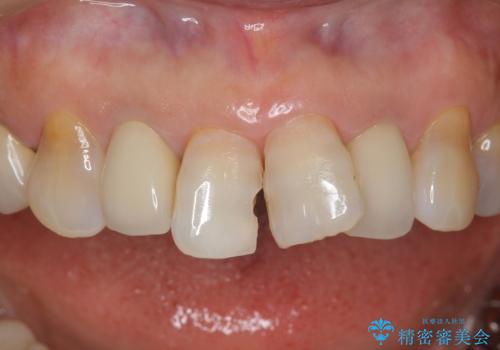

銀歯を白く 虫歯治療

- 30代女性

- 2ヶ月

- 2-5回

- 虫歯治療を希望して来院。

保険適用の銀色のつめもののやり替えを行いました。

- 30.8万円(右上4567 emaxプレスインレー 7万円x4本)費用は治療当時の料金となります